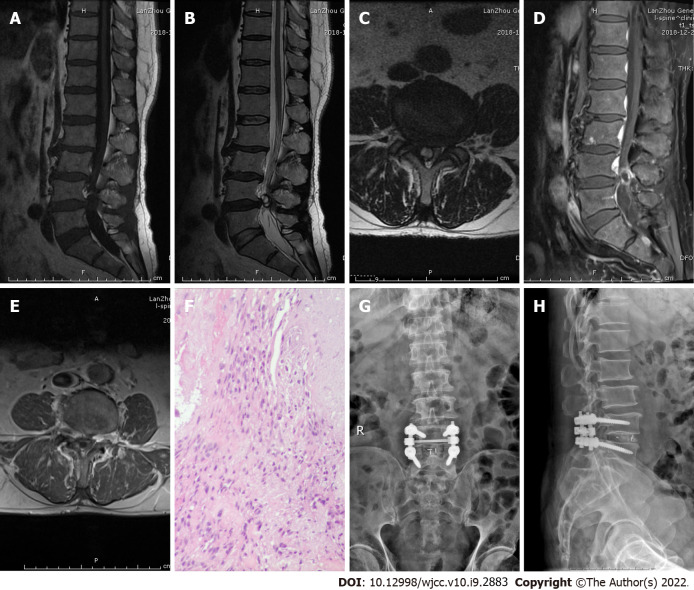

Case 1: After admission, magnetic resonance imaging (MRI) showed an abnormal shadow in the spinal canal of the L4 vertebral segment and compression of the dural sac. T1-weighted images showed high signal intensity, while T2-weighted images showed low signal intensity, with heterogeneous enhancement on contrast-enhanced MRI (Figure 1A-1E).

Imaging examination of case 1. A: T1-weighted preoperative MRI image showing high signal intensity; B and C: Preoperative T2-weighted image showing low signal intensity, and an axial T2-weighted image demonstrating disc fragments in the left posterior epidural space; D and E: Preoperative contrast-enhanced MRI suggested heterogeneous enhancement; F: Postoperative pathology suggested intervertebral disc tissue; G and H: X-ray on postoperative day 2 indicated intact internal fixation.

Case 1: A laminectomy, discectomy, and internal fixation were performed (Figure 1G-1H). The focus was located in the left posterior epidural space, which compressed the dural sac and left L4 nerve root. Postoperative pathology confirmed that the focus was intervertebral disc tissue (Figure 1F).

Case 1 showed high signal intensity on the T1-weighted image, low signal intensity on the T2-weighted image, and heterogeneous enhancement on contrast-enhanced MRI (Figure 1A–1E). Case 2 had low signal intensity on the T1-weighted image, low signal intensity on the T2-weighted image, and heterogeneous peripheral enhancement on contrast-enhanced MRI (Figure 2A–2E). These two cases were diagnosed as neurilemmomas before the operation. Case 3 displayed high signal intensity on the T2-weighted image and obvious peripheral enhancement on contrast-enhanced MRI (Figure 3A–3E). Case 4 exhibited moderate signal intensity on the T1-weighted image and high signal intensity on the T2-weighted image, without enhancement on contrast-enhanced MRI (Figure 4A–4E). These two cases were initially diagnosed as spinal tumors before the operation. Due to the nonspecific imaging findings, we were unable to diagnose these four patients by computed tomography, MRI, or enhanced MRI, so surgery was performed. The focus and adjacent intervertebral disc were resected, the intervertebral space was bone-grafted, and internal fixation was performed. The resected lesions were sent for pathological diagnosis. All four cases were pathologically diagnosed as herniated disc tissue (Figure 1F–4F).